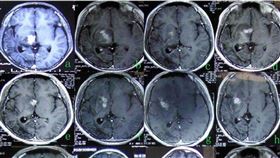

驚!女頭痛2年 開腦抓出27cm「活的」蟲

一位20歲女性,經常性頭疼、頭暈、嘔吐及肢體麻木,曾...

男手腳癱13年 醫開腦活捉「牠」他能走了

大陸廣東廣州有名24歲男子小張(化名),在11歲時出...

20歲妹突半身麻痺!一看腦袋長蟲了

中國深圳一名20歲的葉姓女子,年紀輕輕近日卻突然出現...

頭痛暈眩16年 男就醫發現恐怖真相

想補身卻傷身!位於大陸浙江省衢州,一位28歲的男子,...

腦部遭「蟲入侵」!父後悔給兒亂補身

少女頭痛12年 就醫發現蟲爬腦內

頻頻頭痛要注意,很可能是腦內有寄生蟲入侵!大陸廣東廣...

男腦中揪出7公分「活蟲」!嚇壞醫師

大陸一名男子因平時飲用喝未煮沸的水、吃生肉,結果腦部...